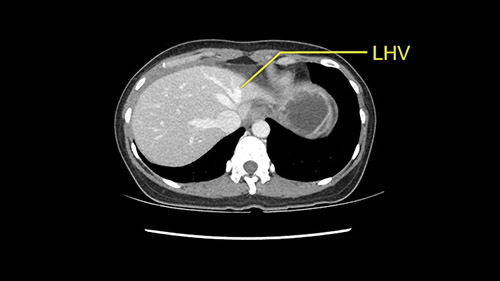

Anatomically, to plan for a left lateral segmentectomy, it’s relatively easy as far as liver surgery goes. I know that I'm going to be looking for the left hepatic vein which will be divided at some point either towards the end at the back near the vena cava or through the middle of the left lateral segment.

I generally take the ligamentum venosum to get access to the left hepatic vein. In this case, not necessarily but we certainly need to think about it.

The transection line will be a little more obvious. There’s a little patch of focal fat here in Segment 4b but we’ll describe the transection line probably through the mid portion of Segments 4a and b up to the top. Up at the top, the left hepatic vein can be taken. There’s a Segment 3 vein or the so-called falciform vein it’ll be rudimentary so I think we’ll be able to get around the left hepatic vein and leave the middle [hepatic] vein intact because it’s free of tumor.

Her vein, it looks like a combined middle and left hepatic vein, it may be encircled during the case as a whole common trunk but most probably it will not be a big deal because if it is okay to go with the left lateral resection, the vein or the left hepatic vein can be catched during the intraparenchymal dissection and can be controlled in that side.

The next step would obviously be the left hepatic vein mobilization. Once you lift the left lateral segment up, and you mobilize from the caudate lobe, you’ll find that you need to identify [Arantius’ canal] and ligate [Arantius’ canal], then only the left hepatic vein comes into view at the apex of the caudate lobe. In this particular case, because the hepatic venous plane is intact and its pretty free, it’s quite easy to ligate the left hepatic vein and staple it off. That would complete the devascularization of the tumor.

The other option of course is to do an anatomical left hepatectomy. In that case, I will start mobilizing of course the left lobe and try to find the ligamentum venosum, take it down and go around the left hepatic vein. I think, importantly in these cases and in this case, as you can see in the venous phase, that’s clearly a moment to stop. Because the left hepatic vein is pretty close to the middle hepatic vein as sometimes it is so you may need to dissect a little bit the parenchyma on top of the left hepatic vein to be able to go around the left hepatic vein safely.